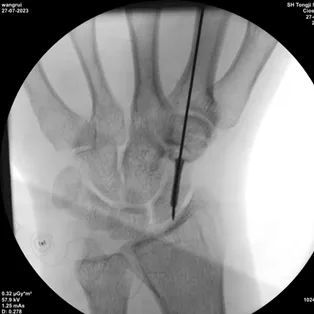

2、沿导板上的孔打入导针,一次成功

3、沿导针拧入加压螺钉完成手术固定